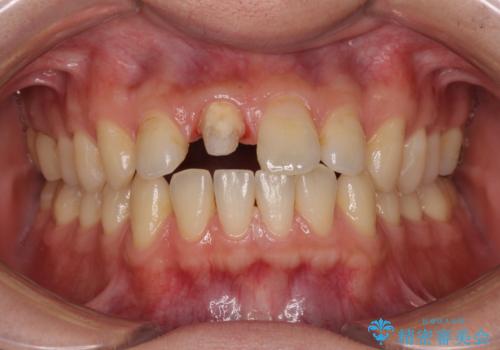

- 数年前に前歯のセラミック治療を行い、そのやり替えを希望して来院された患者様です。

先端が欠けてしまっていて、色も少し不自然な印象があります。

空隙がある歯並び改善のため、矯正治療も提案しましたが希望せれず、隣の歯も一緒に被せものにして、

大きさをそろえることも希望されなかったため、一本だけやり替えていくととしました。